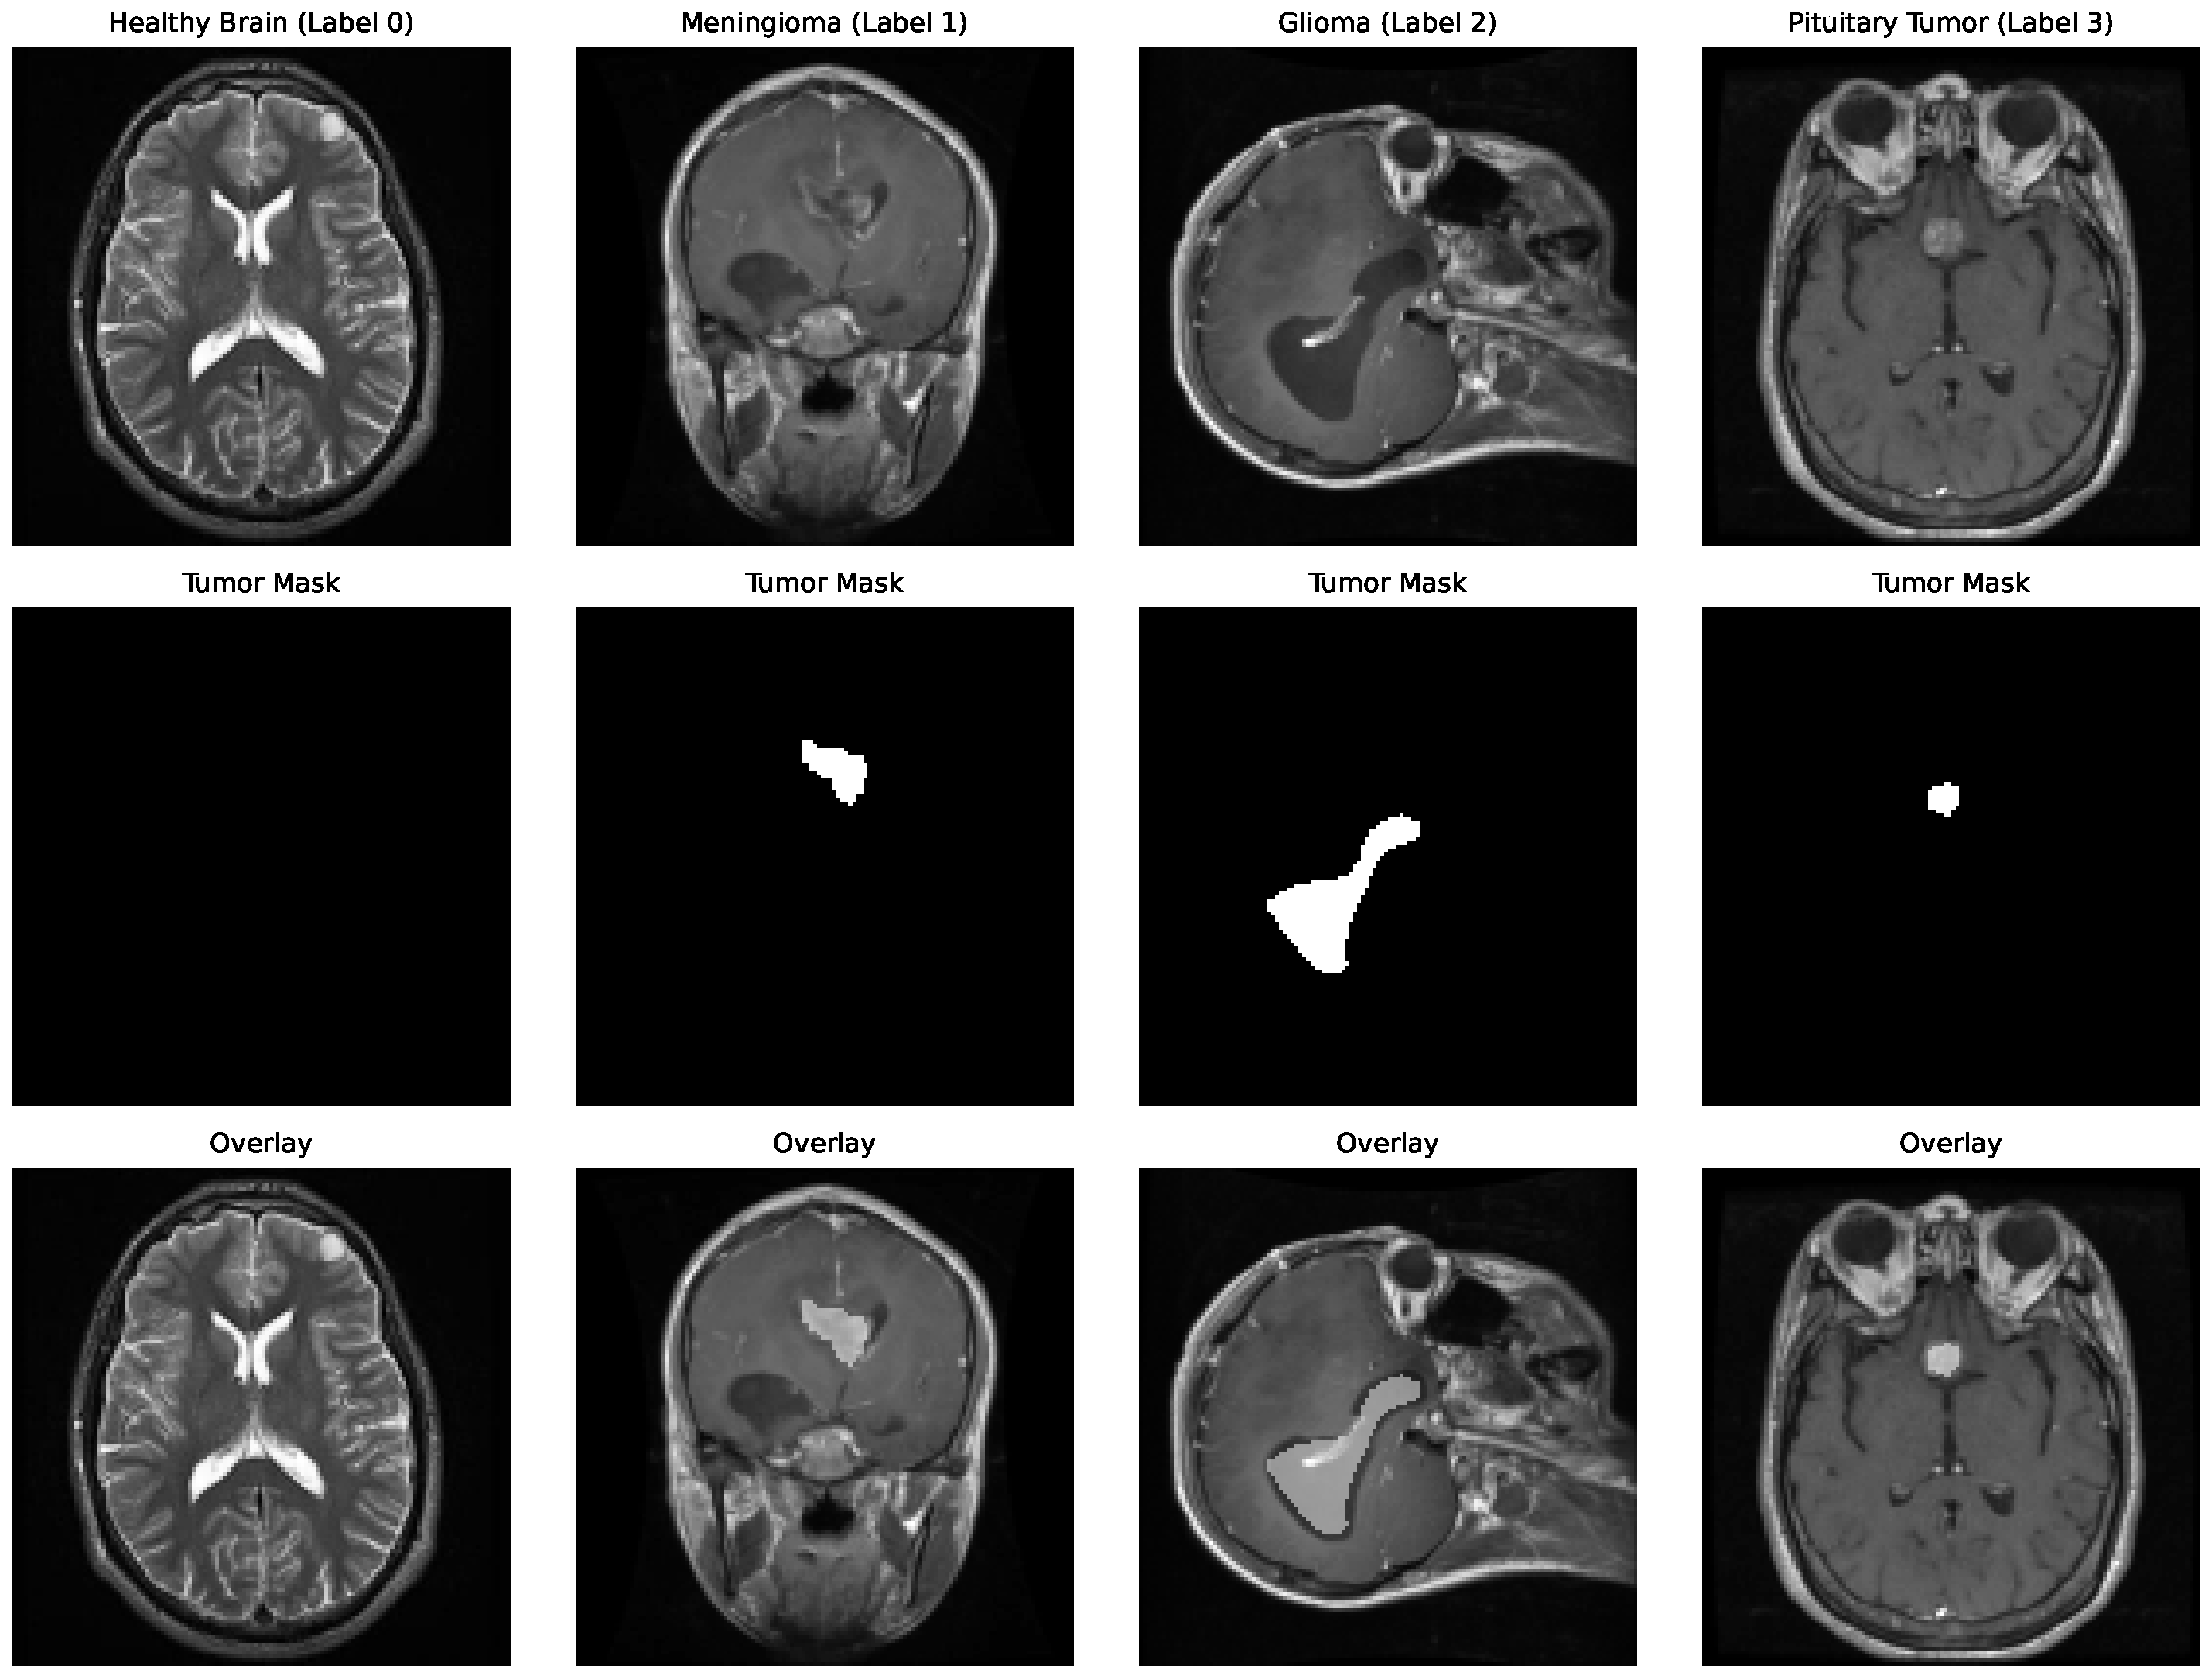

4.1. Dataset Construction and Preprocessing